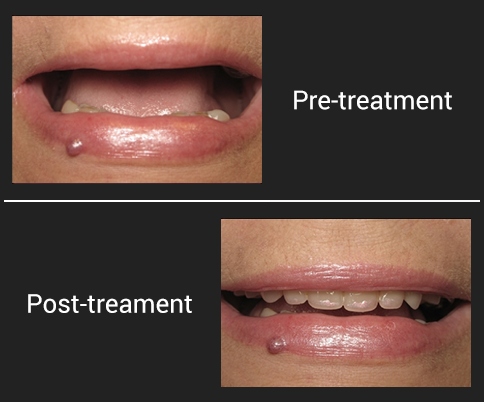

Pre-treatment photograph shows an un-esthetic site. The patient is a 54 year old female who was self-conscious due to her smile. Concerns regarding the economic investment had prevented her from improving her dental condition.

Post-treament photograph shows improved aesthetics. The patient has restored self confidence due to her ability to smile and speak freely with teeth that are stable and aesthetically pleasing.